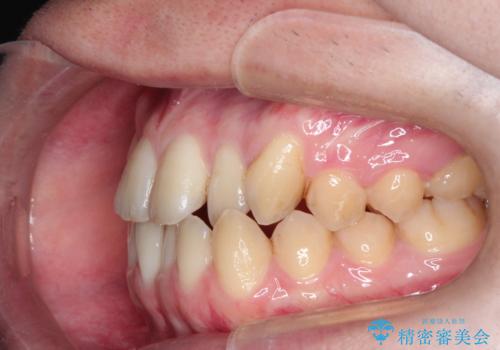

前歯のデコボコ インビザラインによる目立たない矯正

- 前歯のデコボコを主訴に来院された患者様です。

目立たないそうちをご希望されたので、インビザラインにて治療することとしました。

歯と歯の間をわずかに削ってスペースをつくり、デコボコを改善しました。